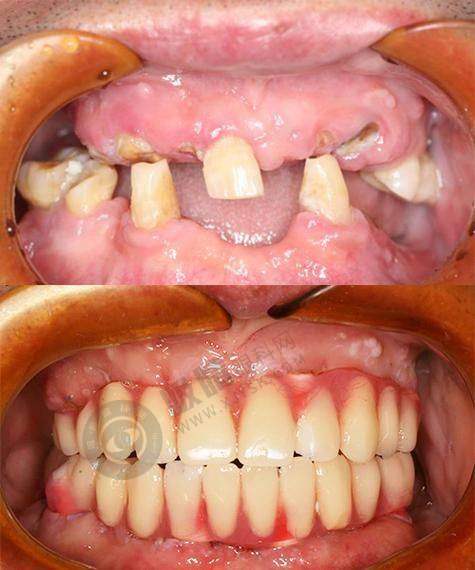

技术优势突出。做种植牙前,使用数字化设备进行详细口腔检查,拍出来的片子更清晰,数据更详细,医生能更清楚了解患者牙槽骨情况,制定更适合的种植方案。同时,引进3D可视化导板技术,能将患者口腔情况以3D形式呈现。医生在手术前可在电脑上模拟种植过程,确定种植体的位置、角度、深度等,手术时按模拟方案操作,能更好地避开重要神经和血管,让手术过程更可控。